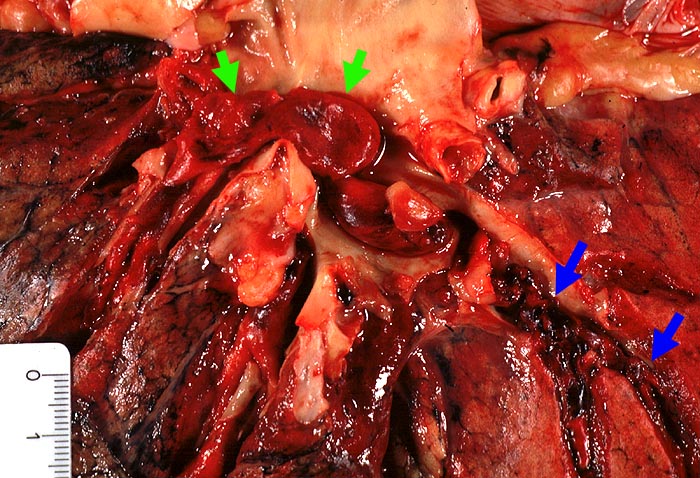

PathoPic ID 1432 - Zentrale Lungenembolie

Zentrale Lungenembolie

Im

►

Hauptstamm der Lungenarterie und

peripher davon liegende Blutkoagel mit matter Oberfläche.

Zusatzbefund

Nicht ganz frische Beinvenenthrombosen der Unterschenkelvenen beidseits.